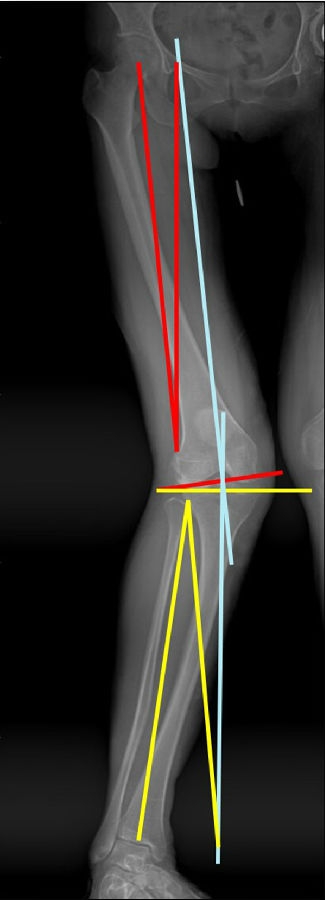

患者二,女性,膝外翻,膝外侧疼痛。通过做畸形分析后发现,该患者同时存在股骨侧畸形、胫骨侧畸形和关节内畸形(LDFA=82°,MPTA=104°,JLCA=6°)。

对于这类病人如何进行术前设计的关键点就在于目标力线应如何设计。要在骨性截骨的时候纠正骨性畸形,关节内畸形要通过关节内的方法解决。因为JLCA不平行,所以要同时画股骨侧关节线和胫骨侧关节线,并垂直于股骨侧关节线做出股骨侧目标力线,垂直于胫骨侧关节线做出胫骨侧目标力线。

根据各自目标力线,分别计算股骨内侧闭合和胫骨内侧闭合角度。

此患者股骨内侧闭合6°,经股内侧闭合13°。

术后影像